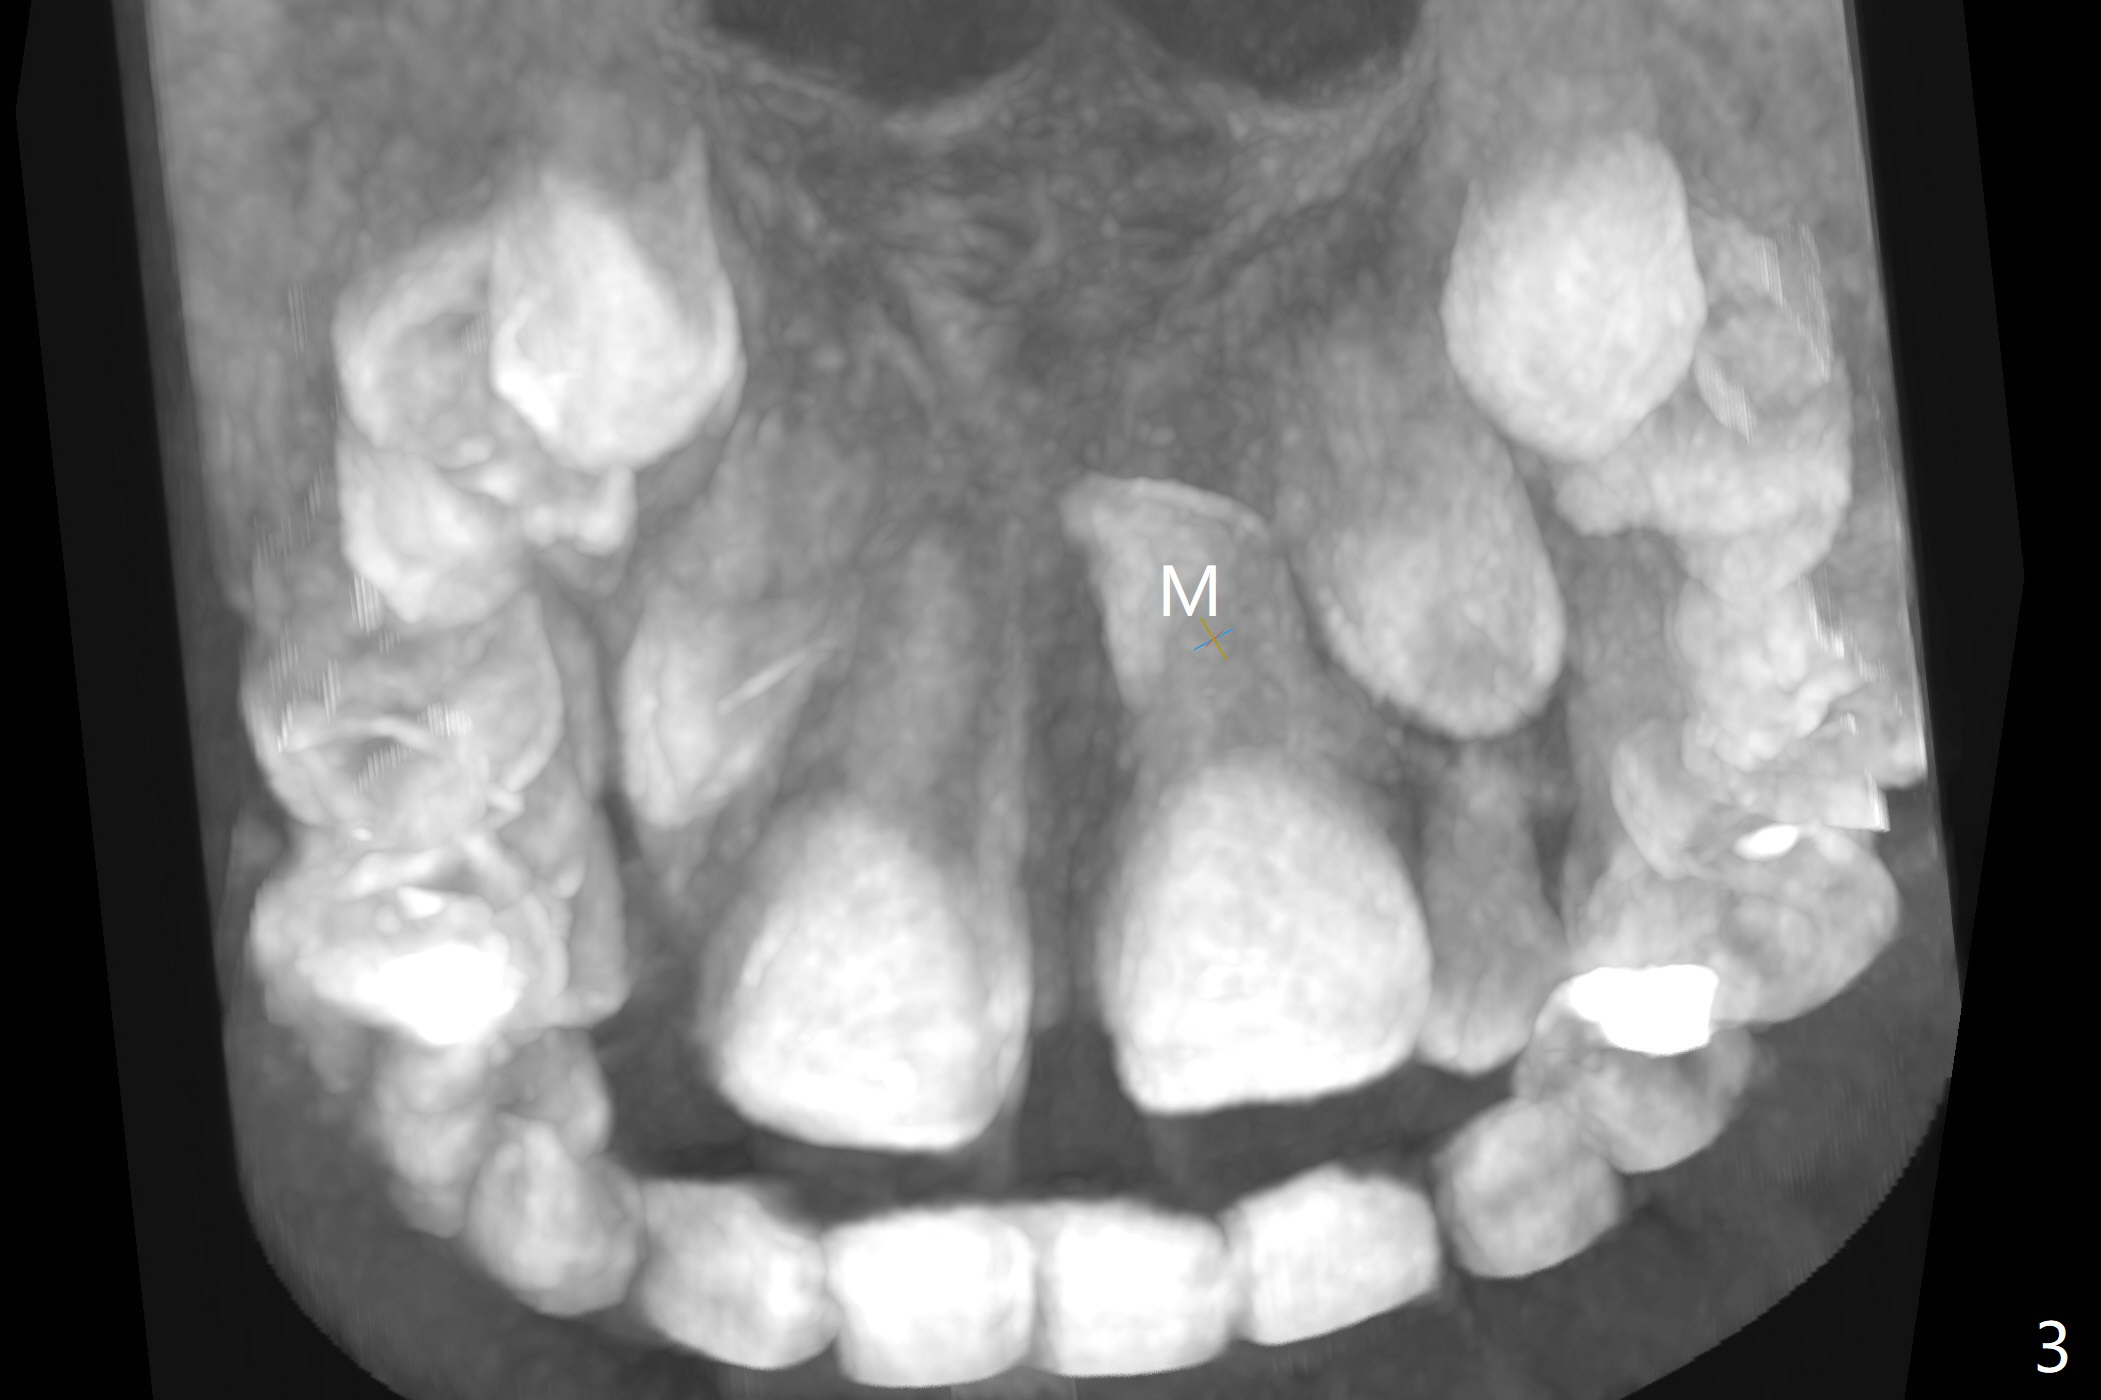

The father of a 7-year-old boy wonders why the upper central incisors, particularly #9, are off (Fig.1 3-D CT tooth coloring). Fig.2 (bone coloring) does not reveal much. Fig.3 (MIP, more transparent) reveals a supernumerary tooth, called mesiodens (M, an extra central incisor, abnormally shaped (cone), near the midline). Palatal view shows that the mesiodens points to the midline and distal (arrow). A palatal gingival sulcus incision will be made to expose the extra tooth (Fig.5). An elevator will be used as midline and distal as possible to avoid damage to the root of #9 and the tooth bud of #10 (Fig.6 MIP). Photos will be taken frontally and palatally preop and after incision and exposure of the mesiodens (palatal).